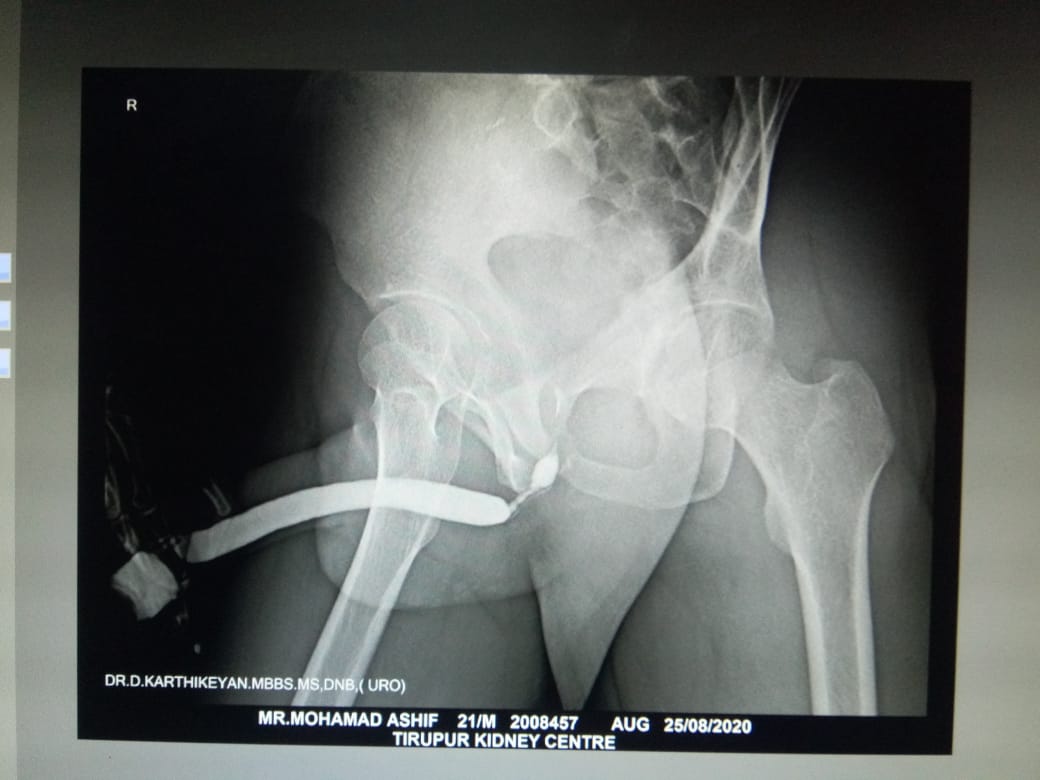

This test is done to access the length severity of narrowing of urethra.., done as an out patient procedure . Retrograde means the dye ( contrast is fluid that can be visualized in x-ray ) is injected ' against the flow ' of urine . syringe loaded with contrast is placed at the tip of penis , slowly injected into urethra , x-ray is taken , so that entire length of urethra is visualized in x-ray